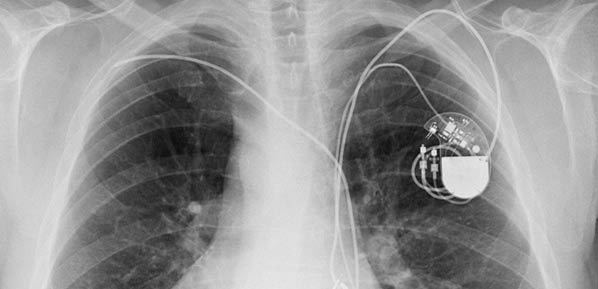

Sometimes, pacemaker and icd leads stop working properly due to damage or scar tissue accumulation. Pacemaker and icd troubleshooting, 2016. Like a pacemaker, an implantable cardioverter defibrillator, or icd, is a device placed under your skin. Implantable cardioverter defibrillators (icds) have a similar appearance to pacemakers. Implanting a pacemaker in your chest requires a surgical procedure. Temporary or permanent modification of the function (i.e., damage). Implantable cardiac conduction devices (also known as cardiac implantable electronic devices or cieds) are a very common medical device of the thorax cardiac pacemakers may be temporary or permanent, with the latter commonly known by the acronym ppm (permanent pacemaker). Pacemaker and icd manufacturers are arranged in alphabetical order with devices organized in numeric sequence.

Die icd elektroden liegen regelrecht im rechten vorhof und im rechten ventrikel. Paces the heart muscles by providing an electrical. Pacemakers and implantable cardiac defibrillators (icds) are widely used for the management of cardiac arrhythmias and congestive heart failure (chf). Implanting a pacemaker in your chest requires a surgical procedure. How does an implantable cardioverter defibrillator work? how will a pacemaker affect my lifestyle? By sorin lazar, henry huang and erik wissner. Accessed on june 11th 2021. Yes an icd and the procedure is at or above the umbilicus as determined by the surgeon, proceduralist or designee. Learn vocabulary, terms and more with flashcards, games and other study tools. Sometimes, pacemaker and icd leads stop working properly due to damage or scar tissue accumulation. Classification follows pacemaker code developed by the north american society of pacing and electrophysiology (naspe) and the british pacing and electrophysiology group (bpeg). Once the wires are in place, your doctor will make a small cut into the. ©2021 daily search trends feedback.

Sometimes, pacemaker and icd leads stop working properly due to damage or scar tissue accumulation. An implantable cardioverter defibrillator (icd) looks similar to a pacemaker, though slightly larger. Which pacemaker/icd is that again. A pacemaker is a small device implanted in the chest. Pacemaker & icd are two different devices. Start studying pacemakers & icds. Movement and/or vibration of the pulse generator or leads. Die icd elektroden liegen regelrecht im rechten vorhof und im rechten ventrikel. Doctors also treat arrhythmias with implantable cardioverter defibrillators (icds). Icds are similar to pacemakers. Another type of pacemaker is called a biventricular pacemaker. Pacemaker and icd troubleshooting, 2016. Paces the heart muscles by providing an electrical.

Icd ( implantable cardiac defibrillator) on the other hand senses a very fast or chaotic rhythm, known as ventricular fibrillation, and gives an electrical. Devices that may interfere with icds and pacemakers. Pacemakers are classified by the nature of their pacing mode. Pertinent factors relating to each manufacturer's devices are referenced according to: 37.71 initial insertion of transvenous lead (electrode) into ventricle 02hk3jz insertion of pacemaker lead into right ventricle, percutaneous approach 37.72 initial insertion of transvenous leads (electrodes). Many devices combine a pacemaker and icd in one unit for people who need both functions. It also contains a computer that tracks your national heart, lung, and blood institute: Pacemaker and icd troubleshooting, 2016.

Implanting a pacemaker in your chest requires a surgical procedure. Pacemaker and icd troubleshooting, 2016. How does a pacemaker work? It also contains a computer that tracks your national heart, lung, and blood institute: Another type of pacemaker is called a biventricular pacemaker. An implantable cardioverter defibrillator (icd) looks similar to a pacemaker, though slightly larger. Once the wires are in place, your doctor will make a small cut into the. Temporary or permanent modification of the function (i.e., damage). ©2021 daily search trends feedback. Pertinent factors relating to each manufacturer's devices are referenced according to: Devices that may interfere with icds and pacemakers. It works very much like a pacemaker. While pacemaker's job is to treat slow heart rate, icd's job is to treat very fast chaotic heart rhythm.